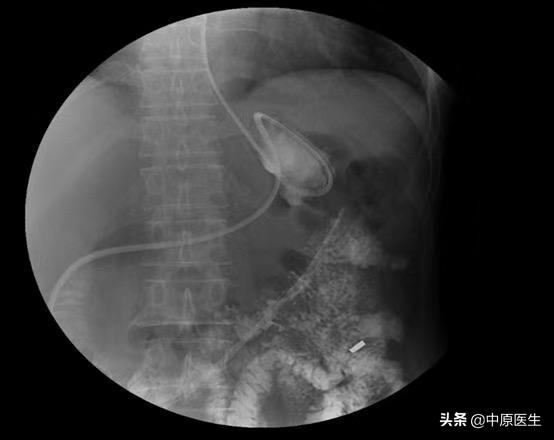

经过思考,我们认为可能与下列因素有关:1、因为是突然出现,是不是空肠营养管脱出?或者是空肠远端梗阻?立即完善胃镜及腹部CT检查,结果未发现空肠营养管脱出,也未发现明显的梗阻;2、难道是导管发生了破损,导致营养液漏到胃内?向空肠营养管内输注少量亚甲蓝,减压管内也引流出了蓝色液体,进一步完善小肠造影,结果回示:营养管瘘,同时也未发现肠道远端梗阻;根据这样的检查结果,我们考虑胃空肠营养减压一体管破损,于是立即行经胃镜给予更换管路。